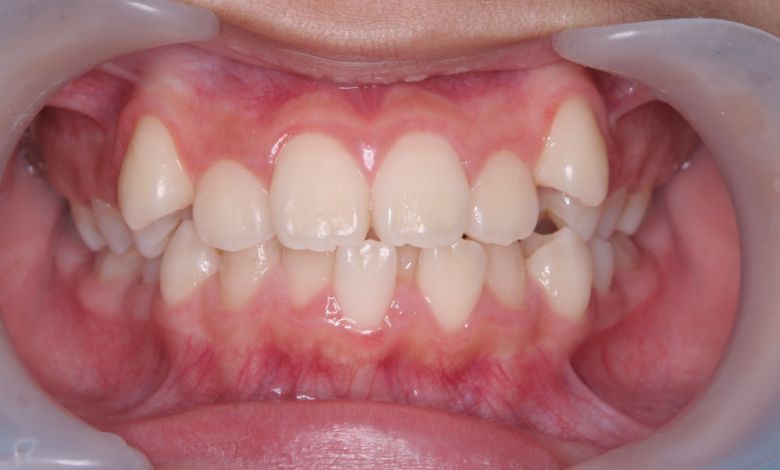

上下ともに歯並びが乱れており、噛み合わせにも大きな不調和が見られる

他院にて上下左右4本の抜歯を前提とした矯正治療を提案されていました。上顎・下顎ともに歯列弓が狭く、

V字型の弓状を呈していたため、叢生(歯の重なり)が強く、噛み合わせにも不調和が見られる状態でした。

上下の咬合関係も不正で、機能的にも審美的にも問題のある状態でした